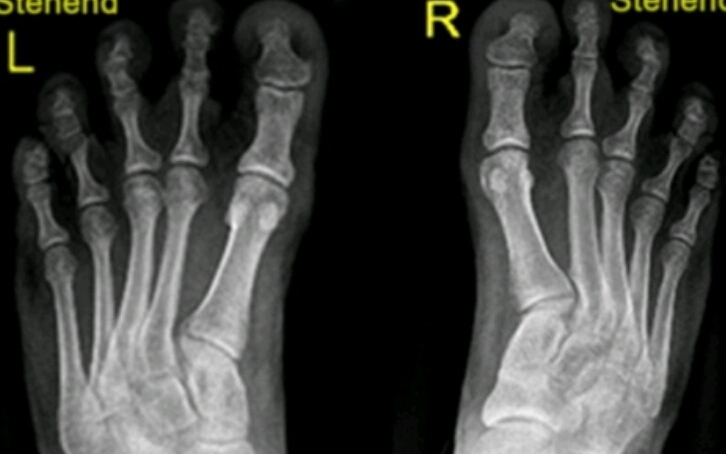

Name the feature. What disease does this represent?

hallux valgus

DJD

Name the feature. What disease is this associated with?

metatarsus varus

Name the feature. What disease does this correlate with?

(Inflammation, pain)

bunion